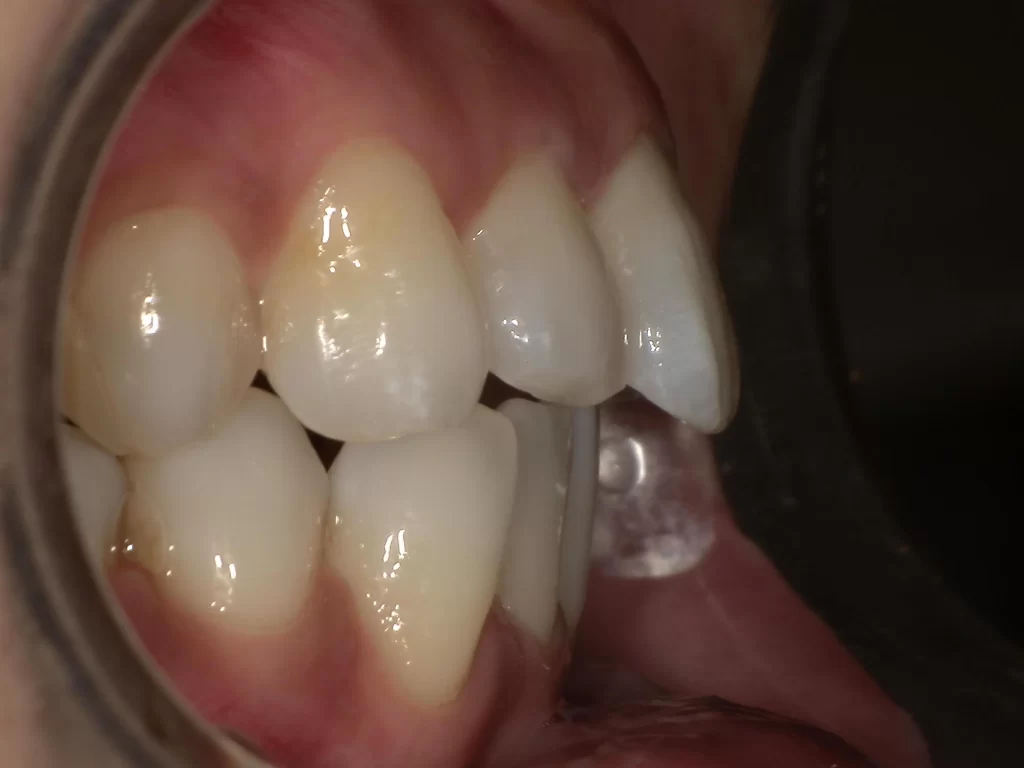

症例③:出っ歯・ガタつき・口が閉じにくい

【期間:9ヶ月経過時 / 費用目安:約45万円】

「出っ歯で口が閉じにくい」「しっかり噛めない」というお悩みで治療中のケースです。

▼ 治療前(Before)

▼ 治療開始から9ヶ月後(現在治療中)

- お悩み: 出っ歯、口元の突出感、ガタガタ(叢生)

- 治療法: アソアライナー

- 経過: 9ヶ月(継続中)

- 費用目安: 45万円程度

- 変化: 前歯の出っ歯感がかなり改善され、自然に口が閉じやすくなりました。奥歯の幅も広がり、しっかり噛める歯が増えてきています。